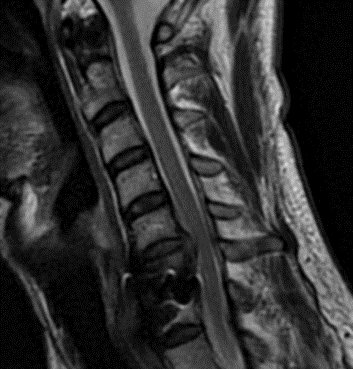

This is a 42-year-old otherwise healthy male who presented electively with progressively worsening neck pain radiating down the left arm, with paresthesia first three digits. He had a previous C6-7 anterior cervical discectomy and fusion (ACDF) two years prior, for which he recovered well. He was referred to Dr. Xavier Gaudin for a neurosurgical spine evaluation. An MRI cervical spine was obtained, which demonstrated C5-6 adjacent segment degenerative disease with a large disc extrusion resulting in severe left lateral recess and foraminal stenosis (Figure 1).

Figure 1: Preoperative MRI demonstrating C5-6 disc herniation with stenosis, adjacent to the previous C6-7 ACDF.